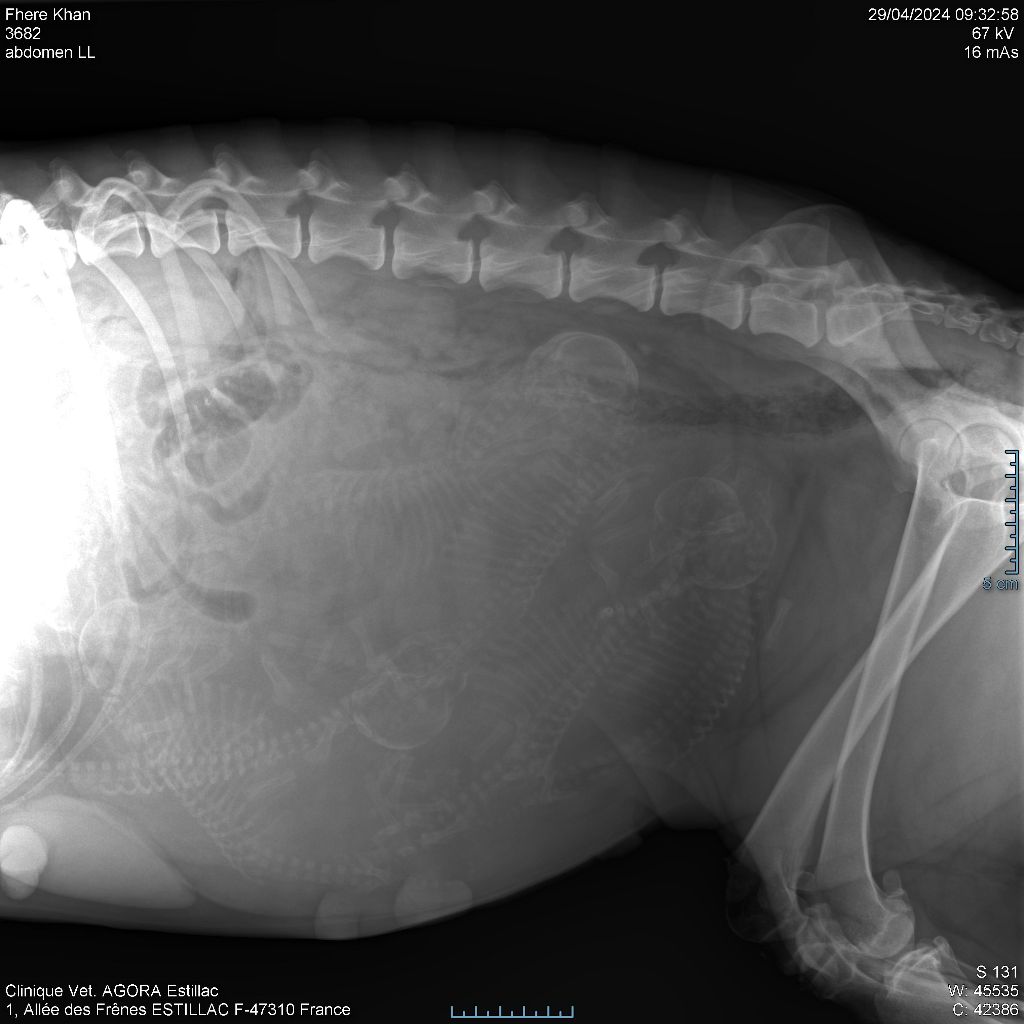

2024 - Les 8 nains de Shere Khan :) Le lendemain de la mise bas Les 8 chiots, 4 femelles 4 males 5 jours avant ;) Même le papa s'occupe de sa progéniture :) Le matin de la mise bas, 9h12, le 1er chiot à naitre. La 1ere sortie femelle fauve collier orange - 9h19 Le 2eme est né - male bringé collier violet - 10h12 Le 3eme est né - male bringé collier bleu - 11h29 Le 4eme est en train de naitre, tout se passe bien. Toujours le 4eme tout juste sortie de sa poche. Le 4eme - male bringé collier marron né à 12h10 18h36 - il y en a 7, au repos après avoir tous tété. 18h30 certainement la fin, le véto avait dit 6 voir 7 :) Shere Khan - une très bonne maman. Radiographie 5 jours avant à la clinique Le vétérinaire en voit 6 voir peut-être 7. 18h50 - Arrivée d'un 8eme. Femelle bringée elle aura le collier jaune Taïko le papa participe ;) Cuvée 2024 Ultime la demi soeur participe aussi :) Une affaire de Famille! On apprend à laper, c'est plus long :) C'est meilleur direct à la tireuse :) On attaque la 4eme semaine ! On est trimballé, maison, remorque, parc :( mais on mange bien :) Maman n'est jamais tès loin :) Notre demi soeur s'occupe de nous aussi. Sous surveillance de Papa :) Notre maître ne fait pas que ramasser nos crottes, il joue aussi :) 4eme semaine avec Maman Papa et notre grande Soeur Ultime :) Notre grande demi-soeur, on l'appelle Tim, c'est plus court. Papa adore faire la vaisselle :) Notre maître passe sa journée à nous compter :) D'ailleur il en manque un, il a du partir en douce, on a rien vu :) Sous la surveillance de Taïko notre Père, attention :) Après une bonne tétée, la sieste avec Maman s'impose :) Voila la pesée, plus de 16,5 kg à nous 8 :) Va falloir trouver mieux que la gamelle pour nous peser :( Atterissage sur le nez. Elle tient pas ta gamelle ! Bhé si ça tient, c'est juste qu'il faut pas bouger :) C'est encore moi le plus gros :) Ma grande soeur m'adore. Elle est super forte :) On peut pas être tranquille :( Tu veux ma photo ?! C'est la récré ! :) Notre grande soeur est top cool! 1, 2, 3, 4, 5, 6, 7, .... il en manque encore un ? Hè j'suis pas en bois ! Patée d'annif, on a 1 mois ! 1, 2, 3, 4, 5, 6, 7, 8. 1, 2, 3, 4, 5, 6, 7, 8. 1, 2, 3, 4, 5, 6, 7, 8. c'est bon ils sont tous là :) Taïko toujours de corvée de vaisselle :) Elle est belle ma Shere Khan! Pesé collier bleu 4630g Pesée collier blanc 4430g Pesée collier orange 4030g Pesé collier violet 4930g Pesée collier rouge 4230g Pesée collier noir 4430g Pesée collier marron 4730g Pesée collier jaune 4430g Sortie quotidienne en famille :)